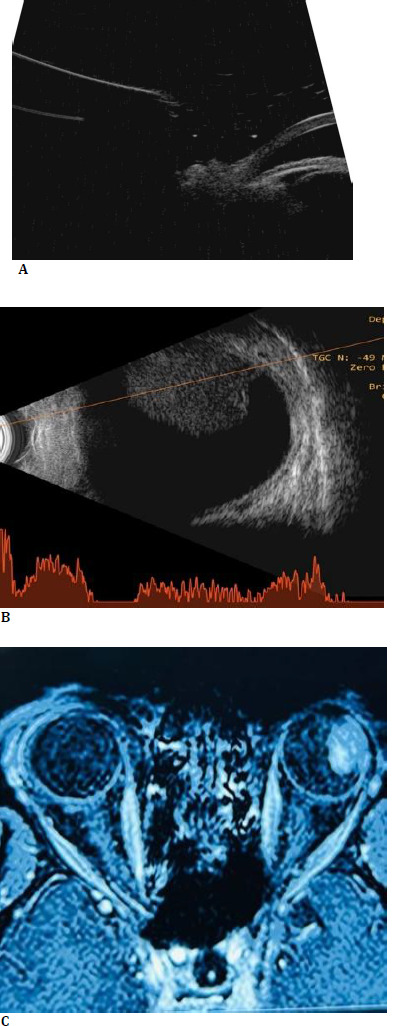

Ciliary body melanoma is a rare and aggressive ocular tumor that often presents with nonspecific symptoms, leading to delayed diagnosis. This report presents the case of a 43-year-old male with a history of ischemic heart disease who presented with diminished vision in the left eye, initially attributed to a cataract. Despite prior evaluation, no sign of malignancy was detected, and the patient was advised to proceed with cataract surgery. The patient visited our center for a second opinion, where a comprehensive evaluation identified a large ciliary body melanoma extending into the anterior chamber. Management was challenging due to the patient's cardiac condition, as anticoagulant therapy could not be discontinued. Enucleation was performed to mitigate the high risk of hematogenous metastasis associated with the tumor's rich vasculature, ciliary body contraction, and potential extension through emissary canals. Histopathology confirmed the diagnosis of spindle cell melanoma. This case highlights the diagnostic complexities of ciliary body melanoma, which can masquerade as a common condition like cataract, emphasizing the need for vigilance in atypical presentations and the importance of thorough evaluation to avoid misdiagnosis. It also underscores the challenges in managing such tumors in patients with significant systemic comorbidities, requiring a multidisciplinary approach for optimal outcomes.